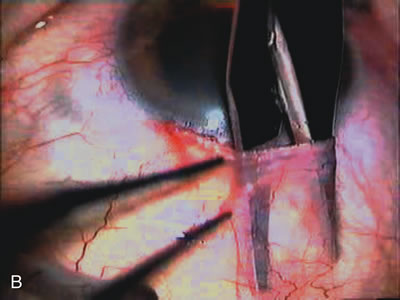

Fig. 4. Viscocanalostomy with deep sclerectomy and phacoemulsification. Nonpenetrating filtration procedures (NPFS) may be combined with phacoemulsification. Patients with mild disc damage and a history of limited topical drug therapy are the best candidates. Patients who require an IOP in the low teens are not good candidates for NPFS. By definition, NPFS is designed to lower IOP without penetrating into the anterior chamber, thereby avoiding the complications associated with trabeculectomy. Viscocanalostomy is intended to allow aqueous to percolate through a trabeculodescemetic membrane into a subscleral cavern created by the deep sclerectomy. The aqueous diffuses from the cavern into the dilated ostia of Schlemm's canal and into the episcleral venous plexus. A. Fashion a uniform 300-micron superficial scleral flap 1 mm into clear cornea. B. Construct a second 600-micron deep flap that facilitates the unroofing of Schlemm's canal, seen as the darker area. C. Use viscoelastic to dilate the ostia of Schlemm's canal. The major problem with viscocanalostomy is the eventual closure of the ostium decreasing flow to the episcleral plexus. D. Dissect the deep flap anteriorly into clear cornea creating the trabeculodescemetic membrane. This membrane is clearly seen between the scleral spur and the bend of the deep flap. The integrity of this membrane ensures the nonpenetrating portion of the surgery. Another problem with NPFS is the eventual fibrosis of this initially transparent membrane requiring goniopuncture. E. Deep sclerectomy gets its name from removal of the deep flap. Removal of this flap creates the potential subscleral space for accumulation of aqueous before it enters Schlemm's canal and exits the episcleral venous plexus. After removal of the deep flap, the superficial flap is sutured into place and conjunctiva closed. Approximately half of these procedures develop a shallow bleb.